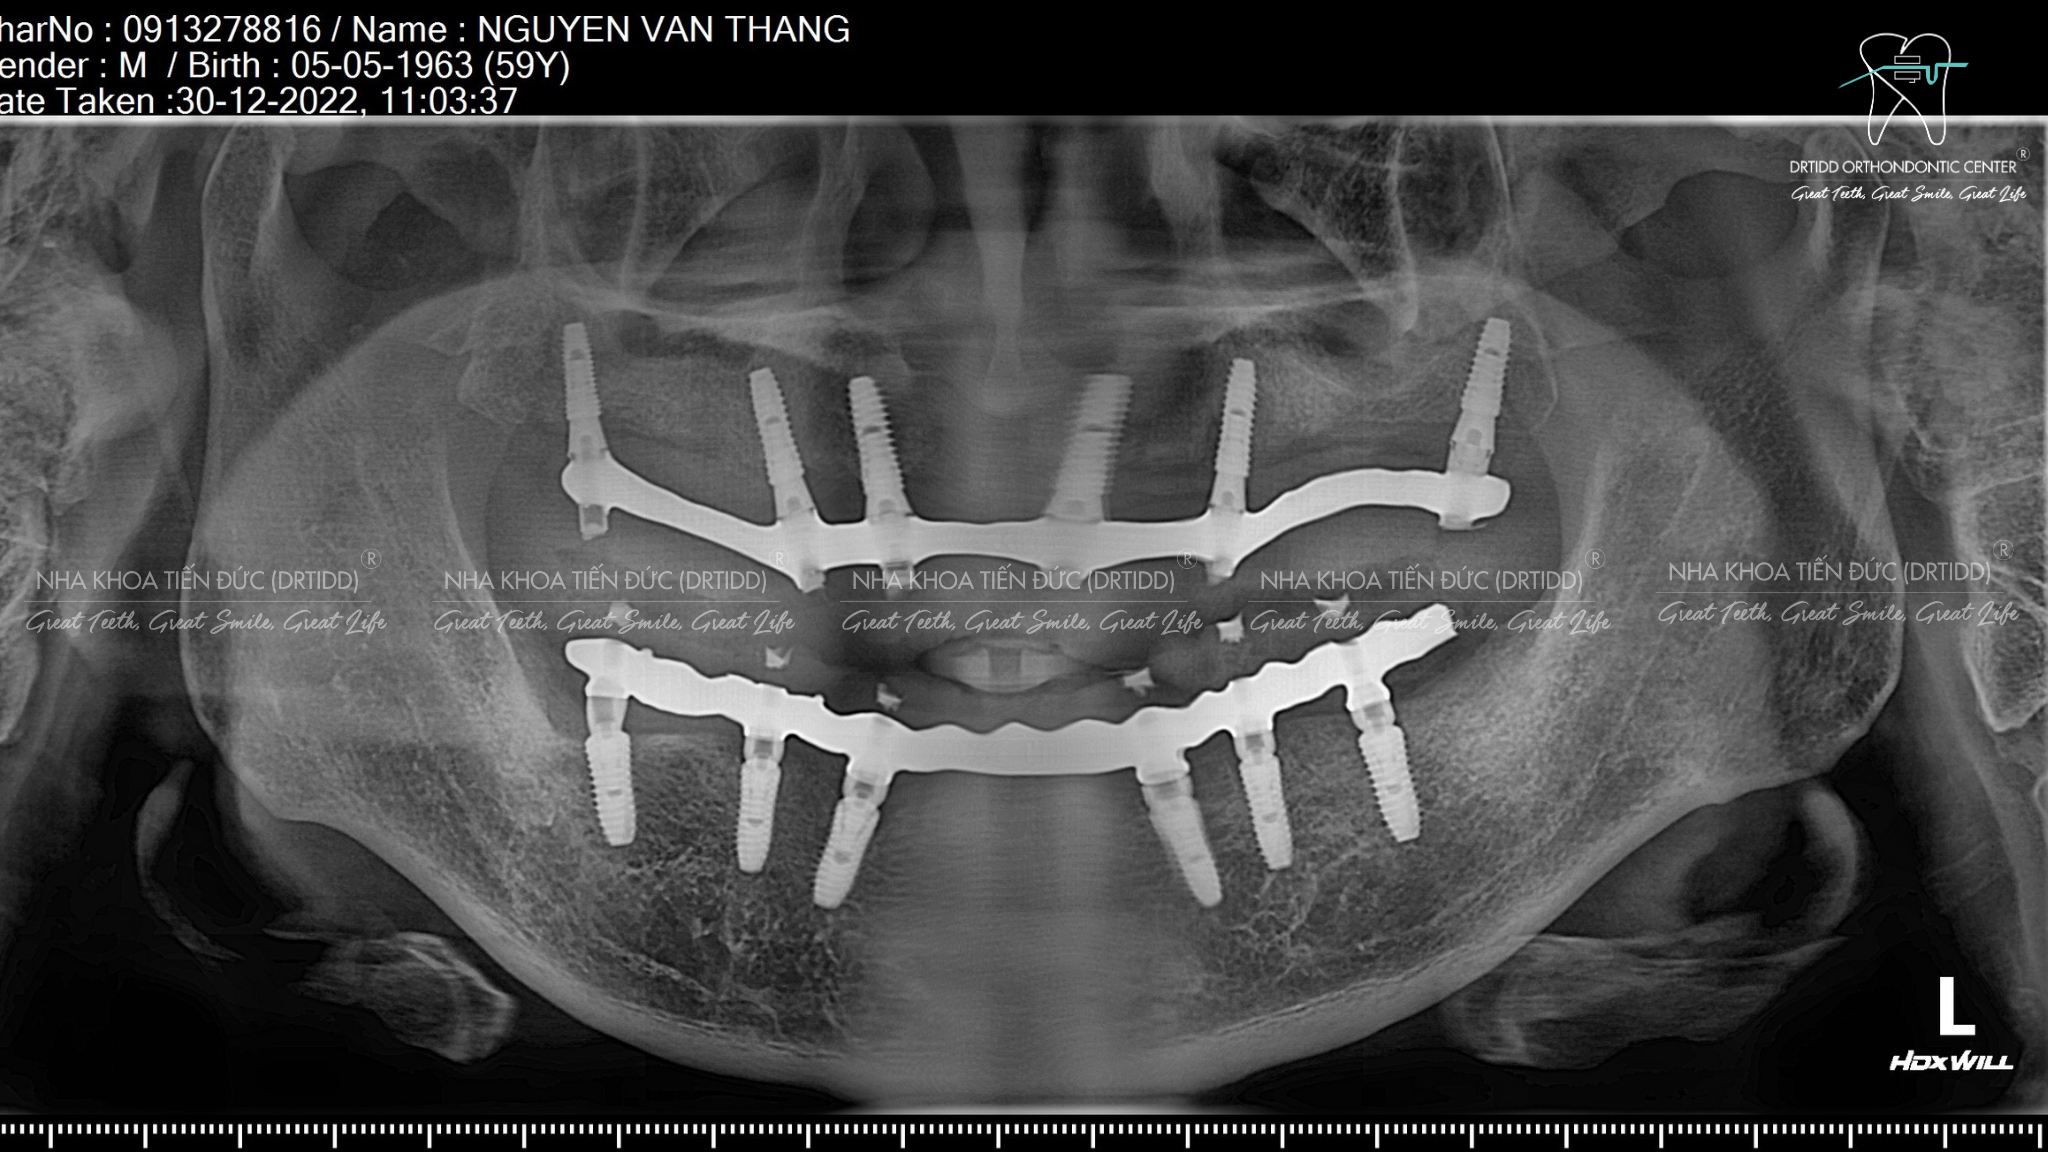

Bệnh nhân sẽ được khám răng miệng tổng quát, chụp ảnh và chụp phim, chụp CTCB cắt lớp để chuẩn đoán tình trạng răng và xương chính xác, đầy đủ.

Sau khi chẩn đoán được tình trạng răng miệng bệnh nhân, bác sĩ sẽ lên phác đồ điều trị cụ thể, dựa vào thể tích và cấu trúc xương hàm, tình trạng răng và khớp cắn, bác sĩ sẽ lựa chọn 4-6 trụ implant phù hợp nhất